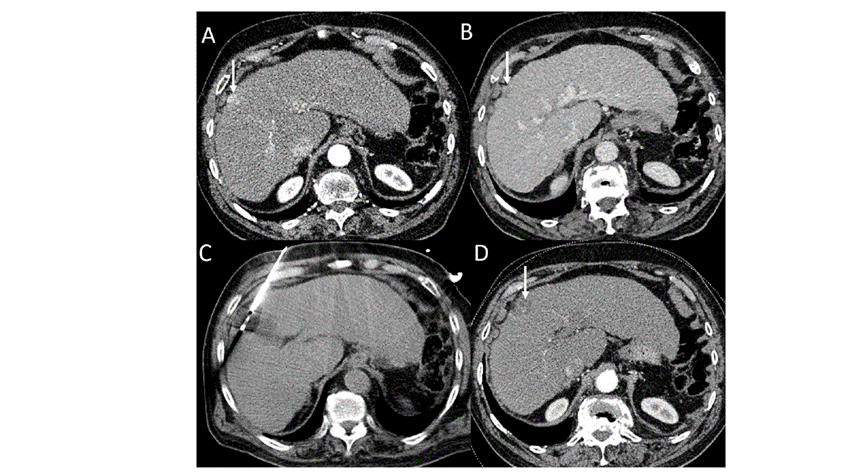

冷凍消融膽囊附近腫瘤病灶

(A)動脈期 MRI 顯示膽囊附近有外周增強(qiáng)病變(箭頭)。

(B)手術(shù)過程中 CT 顯示冷凍探針位于病灶內(nèi)。

(C)消融后,術(shù)后 1 個(gè)月CT 顯示完全消融(箭頭)。

(A)動脈期CT圖像顯示有一個(gè)包膜下結(jié)節(jié)(箭頭)。(B)門靜脈期CT圖像顯示病灶區(qū)(箭頭)。(C) 在手術(shù)過程中的CT顯示一個(gè)冷凍探針位于病灶內(nèi)。(D)消融后,術(shù)后1個(gè)月影像CT顯示完全消融。患者在手術(shù)及住院期間無并發(fā)癥及重大并發(fā)癥發(fā)生。隨訪時(shí)間中位數(shù)為7個(gè)月(范圍:3-12個(gè)月),隨訪期間患者無局部腫瘤進(jìn)展或死亡。